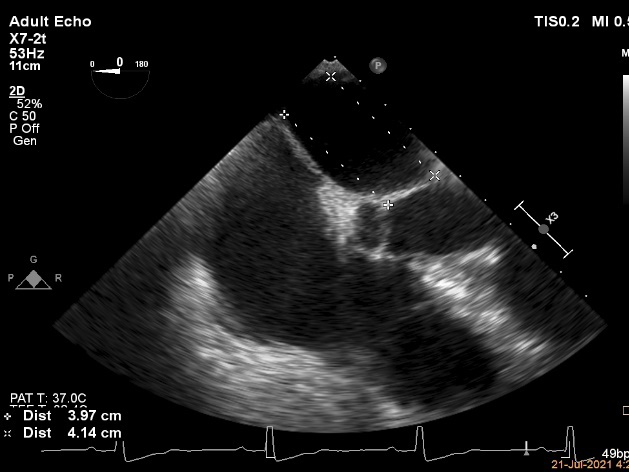

术中超声引导:

确定房间隔穿刺点:靠后

穿刺点高度测量:4.14cm

2D视图下测量大鞘长度2.2cm

2D视图下建立trajectory

3D视图打开夹子

3D视图下调Rotate,定位2区

X-plane:下夹子尝试捕获2区

夹子逐渐夹闭后,2区返流逐渐减少

3D:测量前叶长21.2mm,后叶长10.2mm

X-plane:计算前叶捕获长度6.8mm,后叶捕获长度6.5mm

夹子放置后二尖瓣口平均跨瓣压差:3mmHg

肺静脉血流频谱恢复正常

3D视图下观察二尖瓣双孔形态

3D-color:残余少量返流